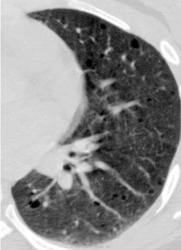

Типичный пример патологии при которой основным патерном являются кисты - :

Лимфангиомиоматоз.

Из архива AFIP. Лимфангиолейомиоматоз.

Лимфангиолейомиоматоз.